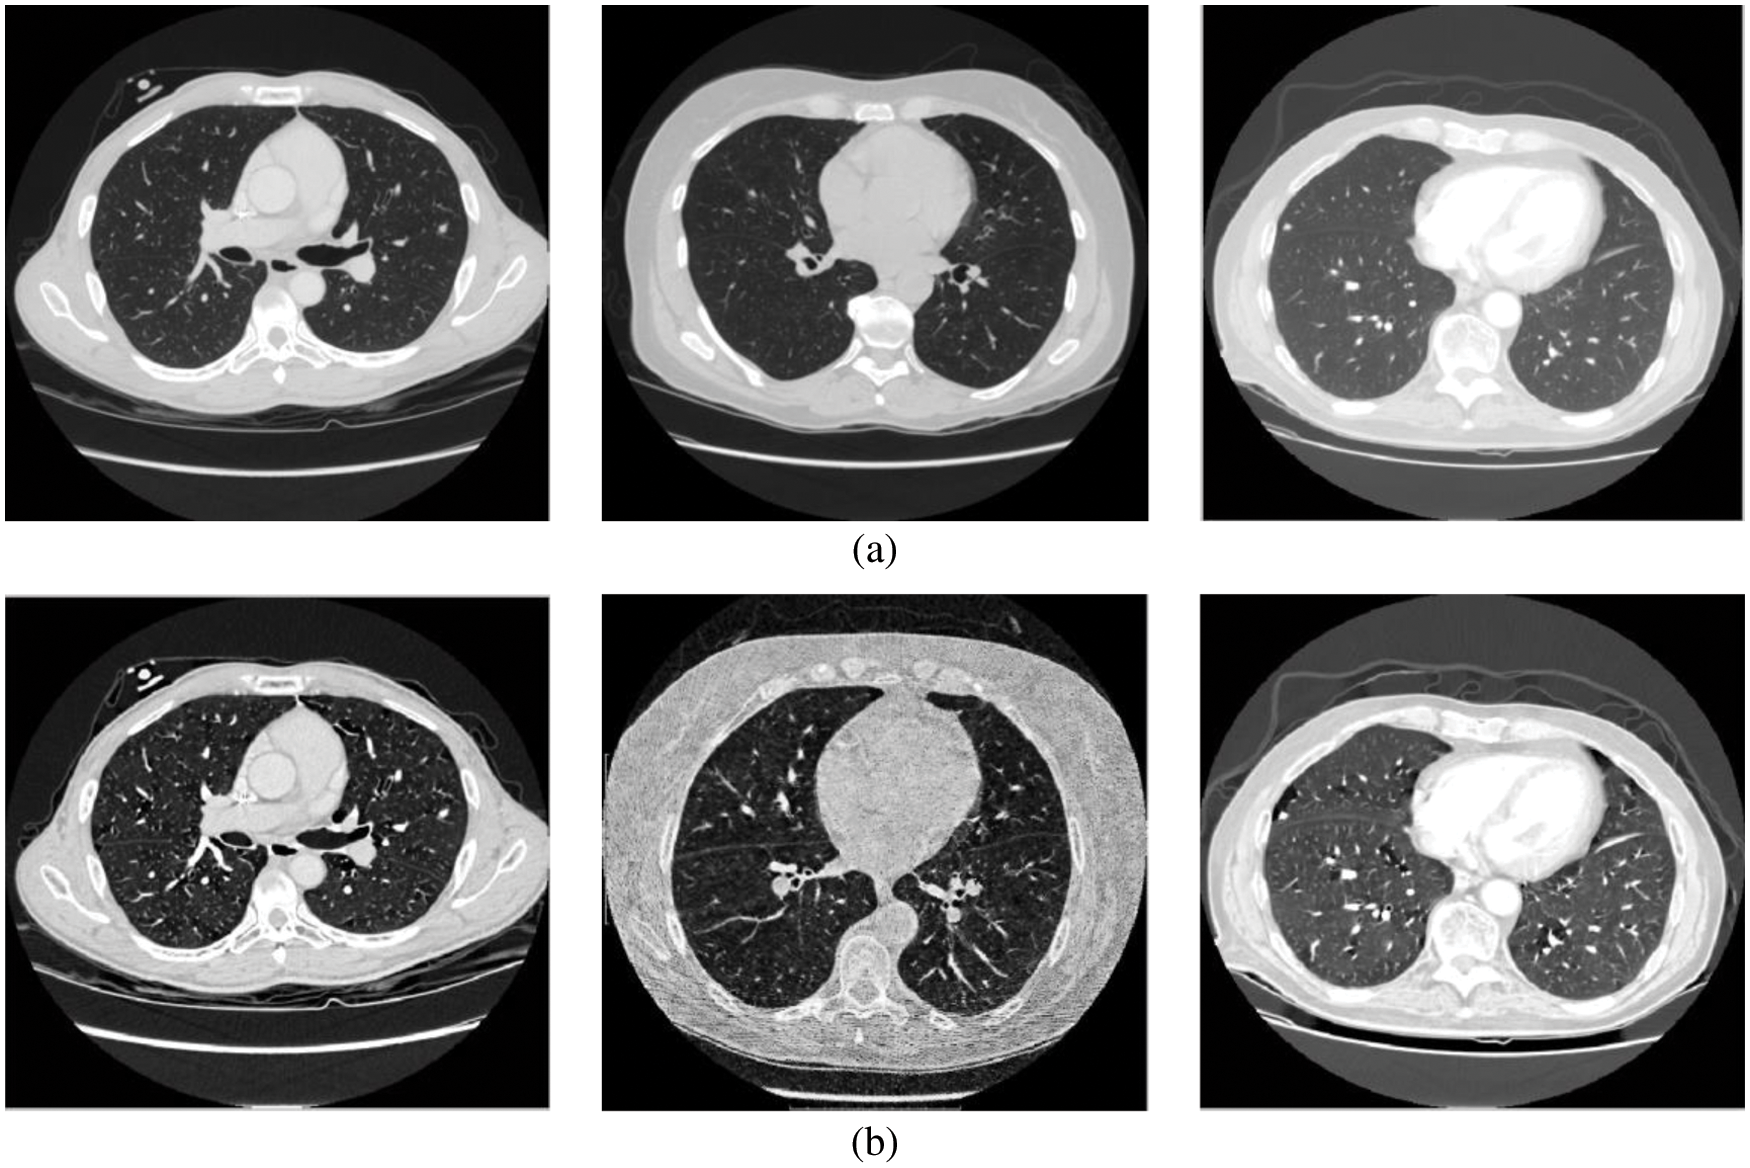

Figure 2: (a) Input CT scans (b) Wiener filtered image

This module employs iterative thresholding and morphological operations to detect the left and right lung regions. The thresholding algorithm selects a gray value (threshold value) for binarization or thresholding of the image, as shown in Fig. 3a. The global thresholding approach cannot adapt to the local variations in the CT lung scans. Thus iterative thresholding [17,18] is applied.

Figure 3: (a) Threshold image (b) Lung region image